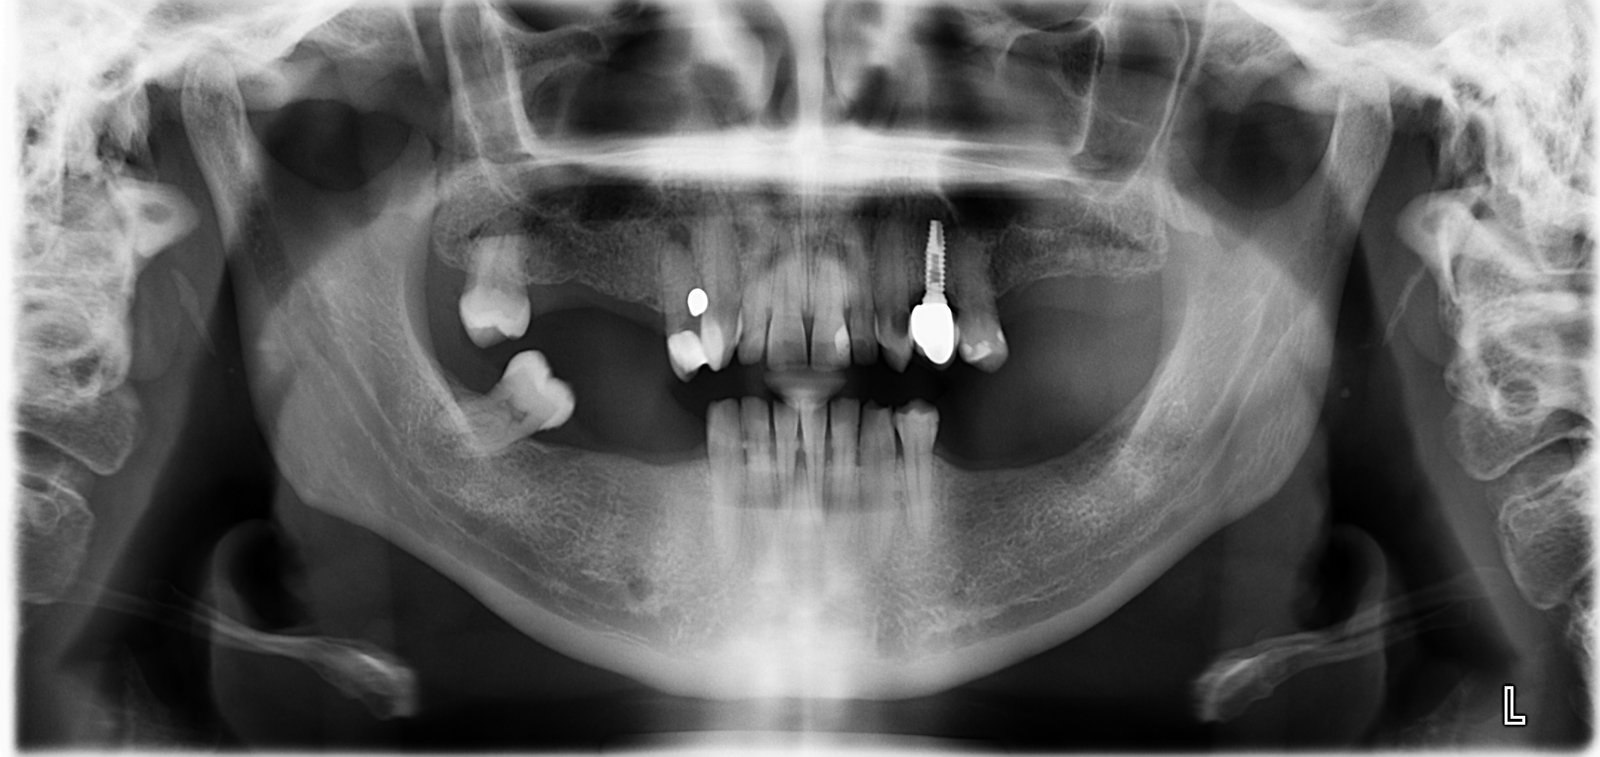

Averiguar Marca de Implante en 24

Buenas tardes, Solicitamos información de la marca del Implante en 24. Muchas gracias. Un saludo.

Según la paciente fue colocado hace unos 15 años, sabéis que implante es??